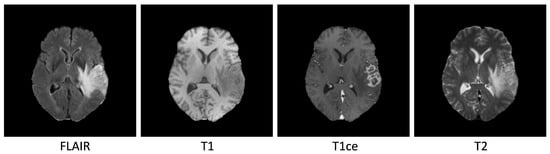

3.1. Data and Preprocessing